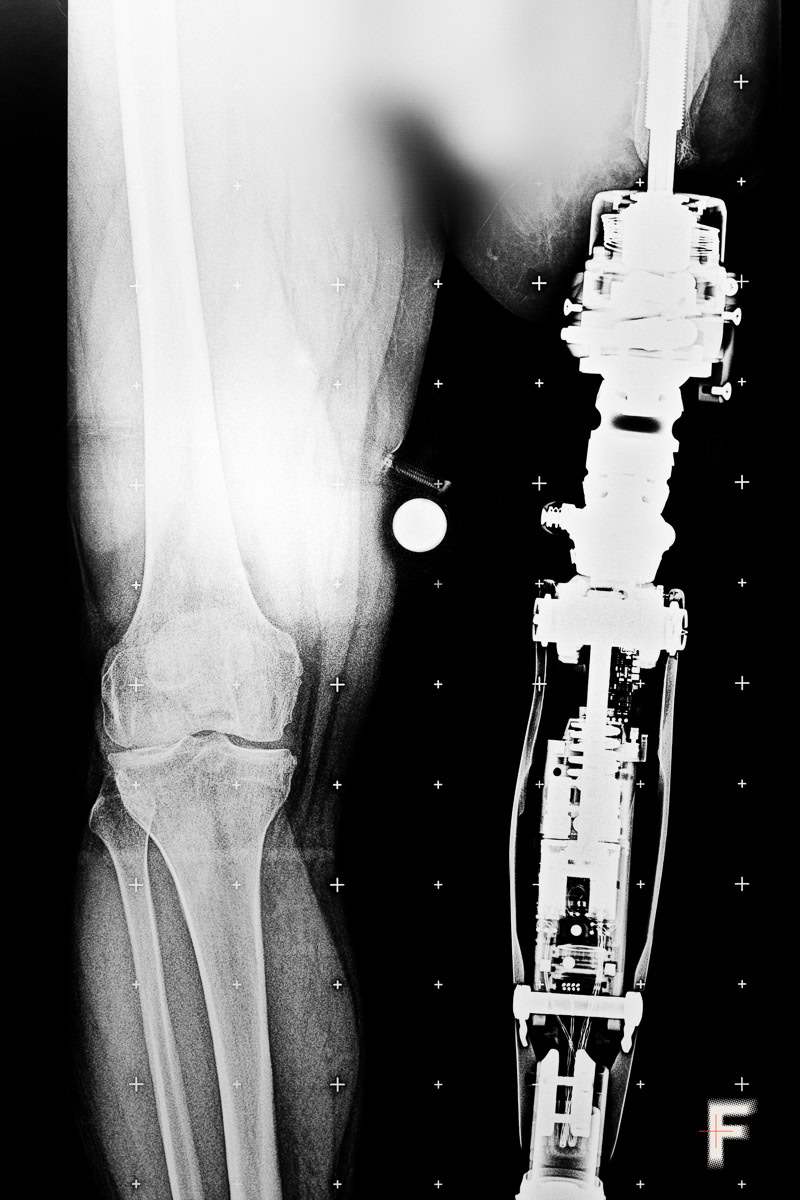

In the first year and a half of the full-scale Russian invasion, the number of amputations in Ukraine reached the scale of World War I. As a result of hostilities and Russian shelling, at least 50,000 Ukrainians have lost limbs, as previously reported by The Wall Street Journal, citing Ottobock, the world’s largest manufacturer of prostheses. About 80% of people with amputations experience pain in the lost limb, and almost all of them feel as if it is still there.

Military serviceman Vadym Sitarchuk underwent a course of ketamine therapy. After being wounded and having both legs amputated, he withdrew into himself: he hardly spoke and avoided communication even with those closest to him. His physical pain was compounded by emotional pain – depression, anxiety, and nightmares.